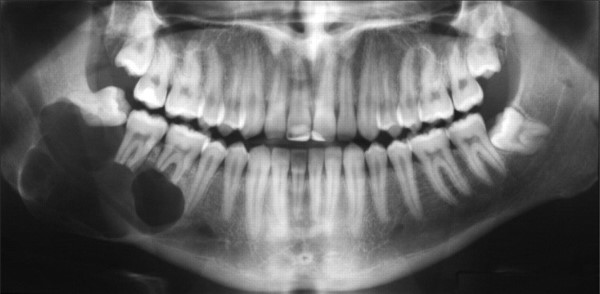

Để chẩn đoán nang chân răng chính xác, bác sĩ nha khoa Quốc Tế Joy sẽ sử dụng phương pháp chụp phim X-quang. Hình ảnh X-quang cho phép quan sát toàn bộ khoang miệng, bao gồm răng, mô mềm, chân răng, xương hàm và tủy răng.

Trên phim X-quang, nang chân răng thường xuất hiện dưới dạng một vùng sáng hình oval hoặc tròn, dính liền với chân răng đã bị chết tủy. Răng thường có lỗ sâu, rộng; vùng chóp răng nằm trong khu vực thấu quang, và dây chằng quanh răng bị giãn rộng.

Trong trường hợp nang chân răng bị nhiễm khuẩn, ranh giới của nang khó xác định hơn do sự giãn mạch và viêm nhiễm. Dựa trên kết quả phim X-quang, bác sĩ sẽ đánh giá kích thước và mức độ nghiêm trọng của nang để lên kế hoạch điều trị phù hợp.